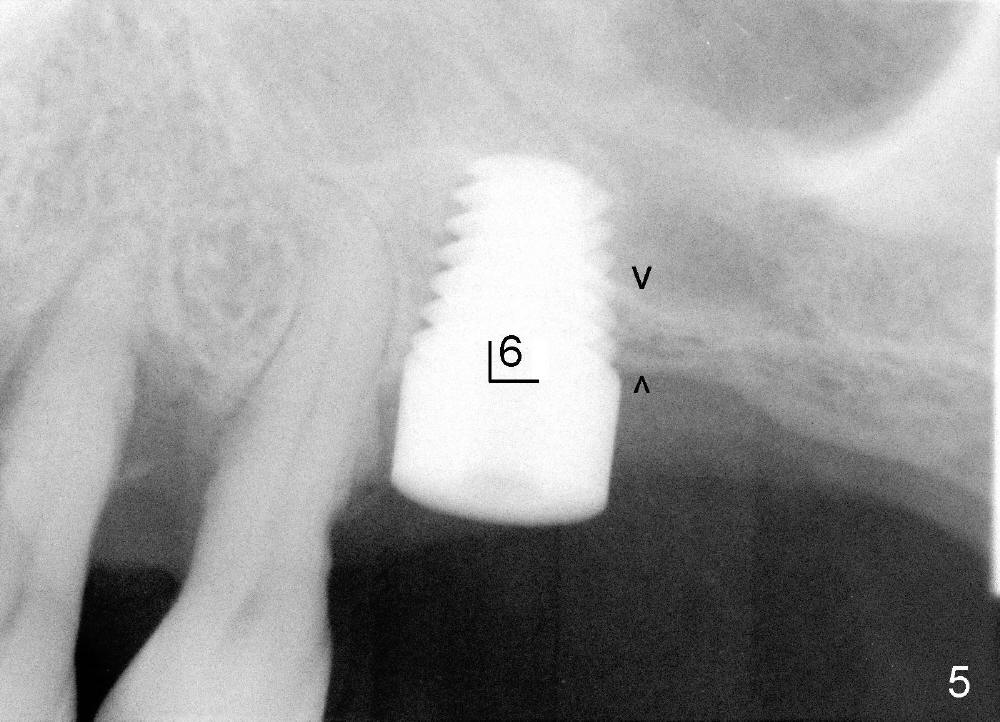

五十来岁吴先生牙周病严重(图一),尤其右上4,5,左上6,最后拔除(图二:远中面观),可见口腔卫生差。先做局部托牙,三年后又失去几个下牙,终于同意植牙。主要困难是上颌窦很低,最好先做上颌窦植骨,但是他胆子特小,多做一个手术对他来说是很大精神创伤,所以壮着胆子先做左上6植牙(图五:7x11mm,torque > 60 Ncm),虽然远中底板不可观(图五箭头之间),但是植牙很牢靠。右侧上颌窦底板更薄,估计不做上颌窦植骨不行,给他吹风说需要做一个手术才能植牙,他竟然同意。但是突然他的托牙(framework removable partial denture)断裂了,断在金属部分(major connector: anterior and posterior bars),说明他咀嚼力如此大,技工室说激光焊接没有保证。我们不得不取消上颌窦植骨,因为它会延迟植牙五六个月,所以我们再次铤而走险在右上第一双尖牙(图三:4, 4x20mm,> 60 Ncm)和第一磨牙(6, 6x11mm,> 60 Ncm)植牙,一个月后在两者之间再植入一个(图四:5,4.5x14mm,> 60 Ncm)。尽管第一磨牙植牙远中骨板相当薄(图四箭头之间),但是它很紧,可能与上颌窦底板坚硬有关。在病人多次要求下,半个月后就装上基牙(图六:2,4,5,6),放置临时牙冠,后三者连在一起(好像牙桥,增加稳定性),这样病人可以正常吃饭。一周后,侧切牙临时牙冠脱落,病人回诊所重新粘固,而右上牙桥仍稳定。